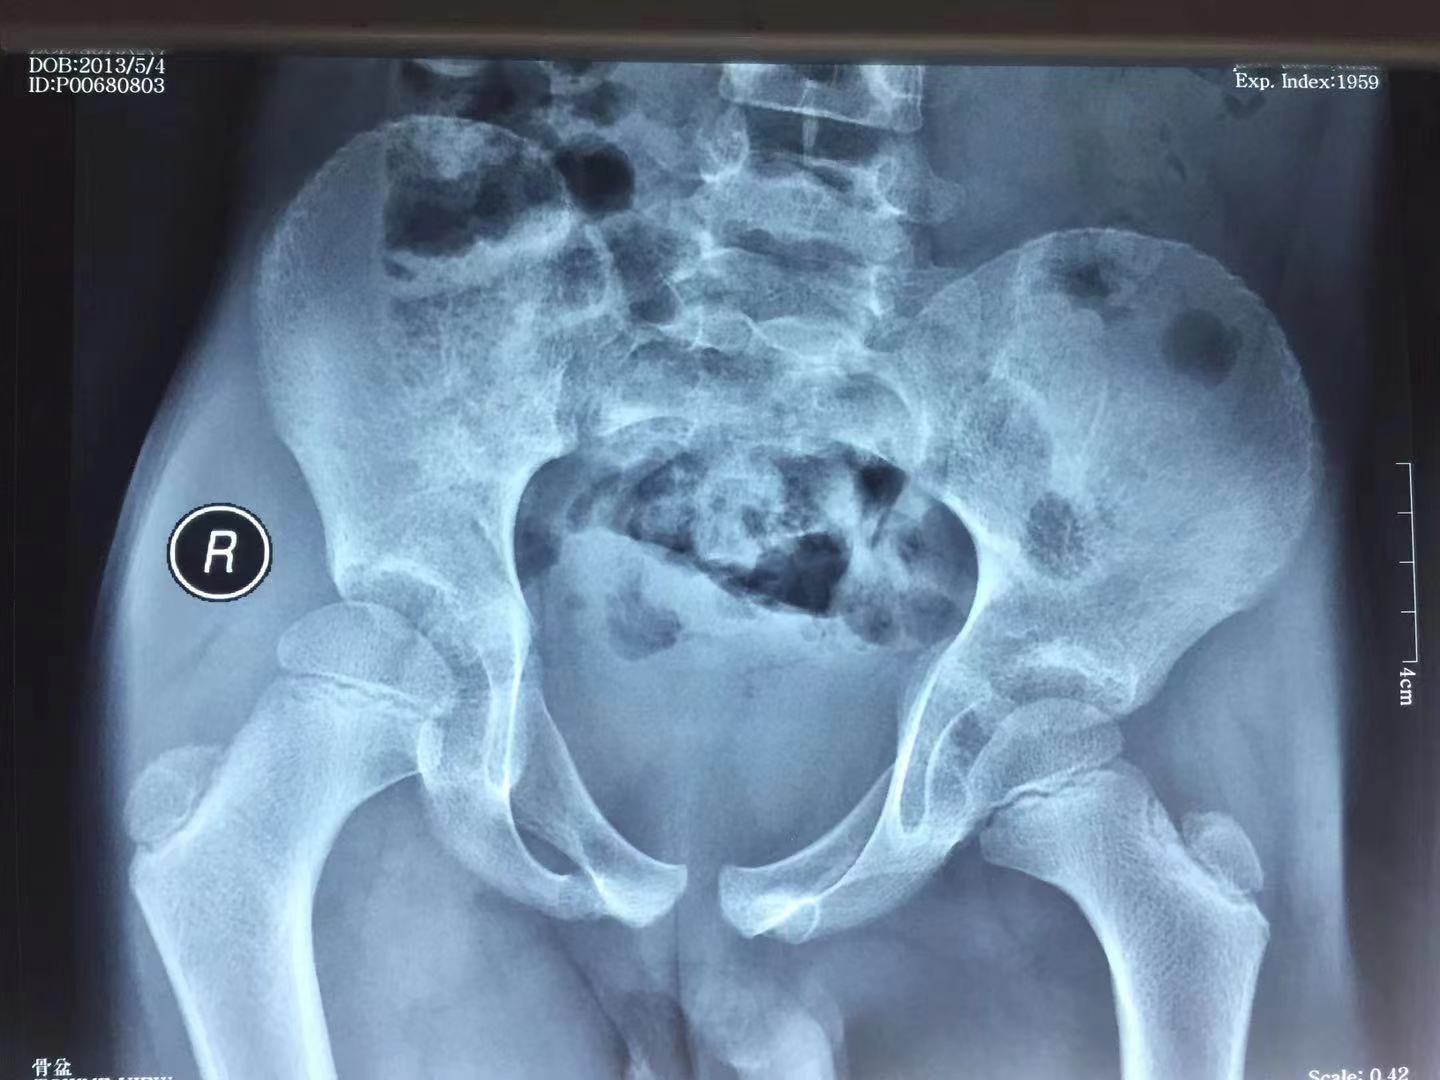

4、影像学检查(1)X线检查 一般骨质无异常表现,有时可表现为骨盆轻度倾斜,髋关节囊肿胀,关节间隙增宽,无骨质破坏。

6、鉴别诊断:1)Perthes病(股骨头骨骺炎)此病虽有跛行,髋部疼痛,但病史较长,X线片可见股骨头骨骺的变形和压缩现象。2)儿童风湿性关节及风湿热该病也常见于儿童,也有髋部疼痛、肌肉痉挛、跛行等症状,但其病情常呈逐渐性进行性发展,实验室检查白细胞数及血沉可有升高,且本病多累及多个关节。3)化脓性关节炎该病也有髋部疼痛、跛行、骨盆倾斜,但其体温高于正常,血象亦高于正常值,而且病情较重,髋关节穿刺可抽出脓液。4)髋关节结核为慢性疾病,病史长,并可同时表现出结核的全身症状。5)小儿先天性髋关节脱位跛行明显,“4”字试验阳性,如为单侧发病,则双下肢不等长,但无明显髋部疼痛、肌肉紧张、压痛阳性,X线片有特殊表现。